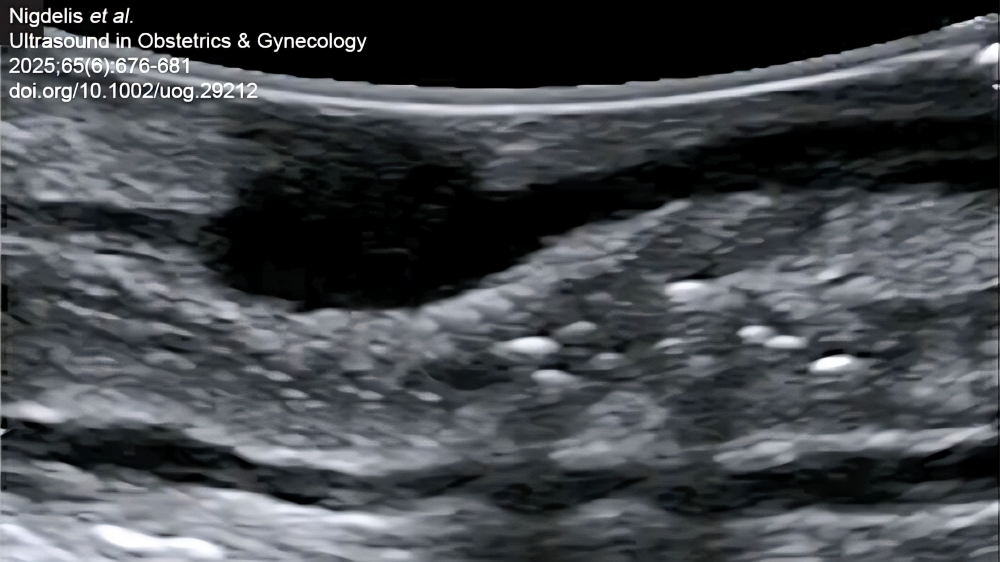

“Endometriosis is a complicated and growing health concern that affects approximately 2–3% of females at birth worldwide. Despite advances in imaging, transvaginal ultrasound for deep endometriosis (DE) is prone to limitations, necessitating use of innovative tools, such as intraoperative ultrasound (IO-US), to improve planning and decision-making.

This EndometriosisAwarenessMonth, read more on this topic by checking out the article by Nigdelis et al., which summarises evidence on the use of IO-US in surgery for DE, and its applicability in disease management.

Title: Intraoperative ultrasound in minimally invasive surgery for deep endometriosis: time for new approaches

Authors: M. P. Nigdelis, G. Hudelist, J. Keckstein, E.-F. Solomayer, A. Daniilidis, H. Krentel, A.-S. Constantin